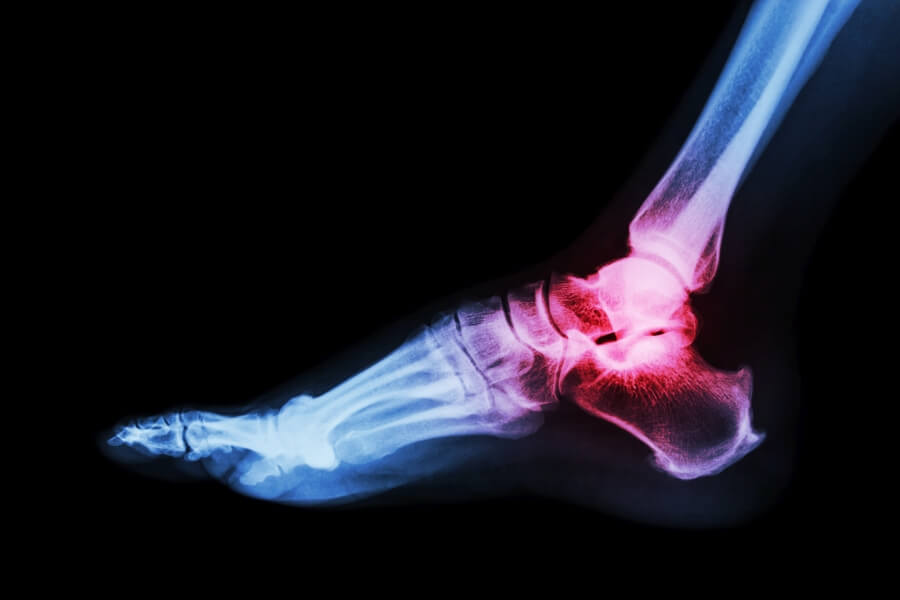

Dna moczanowa, znana również jako skaza moczanowa, podagra (gdy atak zapalenia obejmuje duże palce u stóp) lub artretyzm to choroba reumatyczna objawiająca się silnym bólem oraz zapaleniem i zniekształceniem stawów. Główną przyczyną choroby jest podwyższony poziom kwasu moczowego we krwi (hiperurykemia). Najczęściej atakuje ona staw śródstopno-paliczkowy dużego palca u stopy, ale może dotyczyć też innych np. stawu łokciowego, stawu kolanowego czy stawu barkowego.